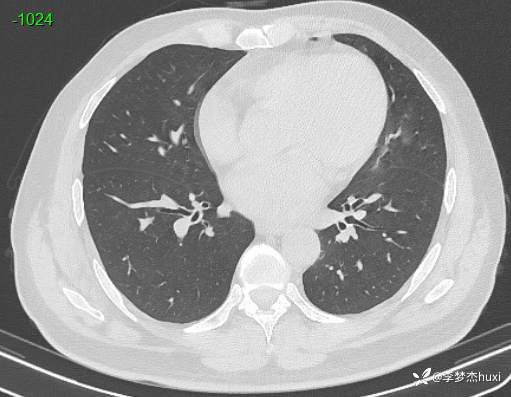

男性48岁,咯血3小时,咯血病因?

主诉:咯血3小时

简要病史:患者于入院前3小时无明显诱因出现咯血,为鲜红色,量较多,约10ml,伴胸闷、压气,伴咳嗽,无明显咳痰。

体格检查:T36.2℃,P110次/分,R20次/分,BP250/130mmHg。神清,呼吸平稳,浅表淋巴结不大,双肺叩清音,双肺未闻及干湿性啰音,心率110次/分,律齐,无杂音。腹部平坦,软,全腹无压痛,无反跳痛及肌紧张,肝脾肋下未触及,双下肢无水肿。

辅助检查:胸部CT:双肺炎症,双肺纹理增多,主动脉及冠状动脉钙化,主肺动脉稍增粗,右侧肾上腺点状高密度影,考虑脂肪肝。

临床诊断:肺炎咯血